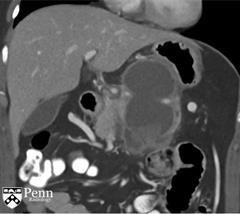

马女士, 55岁,左腰痛。腹部增强CT如下图所示。

于胰体/尾部的巨大的分叶状的囊性肿块,包绕脾动脉。其内可见一致密物在病变的内部下方与其分层。脾静脉内形成血栓,导致明显的胃肝和胃脾静脉曲张。见一假性动脉瘤起源于脾静脉的分支。

诊断:粘液性囊性肿瘤伴低度不典型增生,仅局限于胰腺,邻近慢性胰腺炎和假性囊肿形成伴囊内血栓。